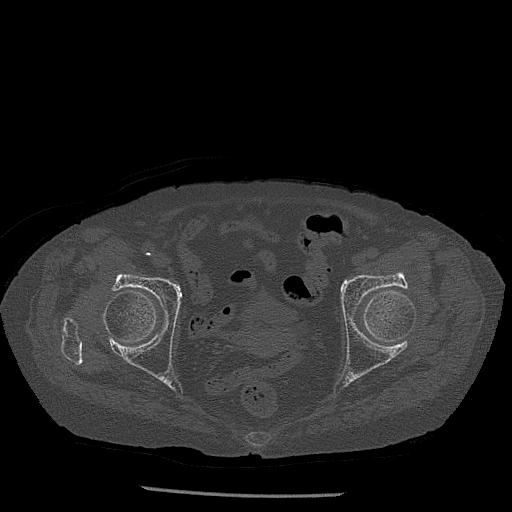

100703 1/27 両股正面+軸 1/29 両股正面+軸 94歳女性 パンソンロン